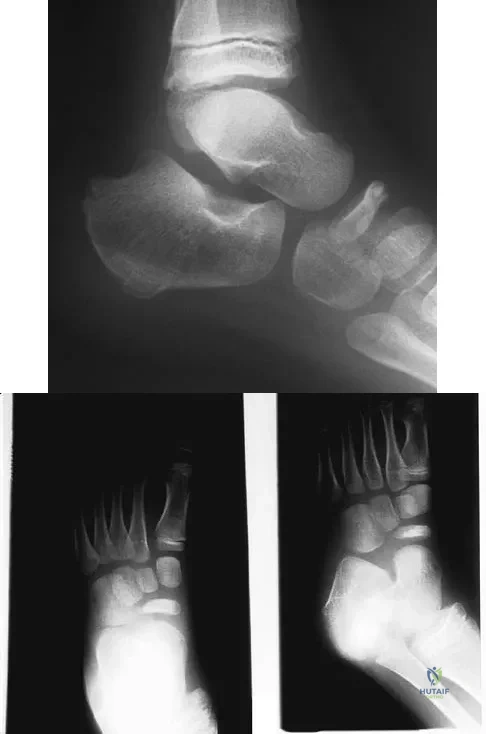

Question 8

A 5-year-old boy has had midfoot pain with activity for the past 3 months. He has no pain at rest. Radiographs are shown in Figures 29a and 29b. Management should consist of

Explanation